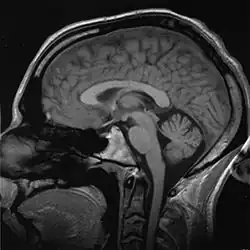

Medical imaging

Medical/biomedical imaging is a major segment of medical devices. This area deals with enabling clinicians to directly or indirectly "view" things not visible in plain sight (such as due to their size, and/or location). This can involve utilizing ultrasound, magnetism, UV, radiology, and other means.

A T1-weighted MRI scan of a human head, an example of a biomedical engineering application of electrical engineering to diagnostic imaging. Click here to view an animated sequence of slices.

Imaging technologies are often essential to medical diagnosis, and are typically the most complex equipment found in a hospital including: fluoroscopy, magnetic resonance imaging (MRI), nuclear medicine, positron emission tomography (PET), PET-CT scans, projection radiography such as X-rays and CT scans, tomography, ultrasound, optical microscopy, and electron microscopy.